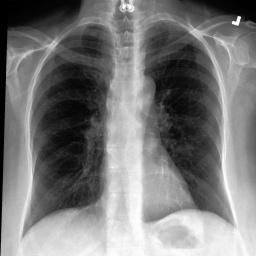

Refer to caption

Train

Valid

(a)XR(a)X_{R}

Test

(b)X^R(b)\hat{X}_{R}

(c)XA:ut(c)X_{A}:\mathcal{L}_{ut}

id\mathcal{L}_{id}

ut+id\mathcal{L}_{ut}+\mathcal{L}_{id}

Fig. 3: Anonymization results. Real images XRX_{R} randomly selected from the training, validation, and test sets are displayed in the first column. The corresponding reconstructed images X^R\hat{X}_{R} are displayed in the second column. The anonymized images XAX_{A} are displayed in the last three columns.

Qualitative Results The visualization results are shown in Fig. 3. In this figure, the anonymized images optimized using only the utility loss ut\mathcal{L}_{ut} (column 3) exhibit greater visual similarity to their real counterparts (column 1), while those optimized using only the identity loss id\mathcal{L}_{id} (column 4) appear more distinct from their originals. Additionally, the anonymized images optimized with both the ut\mathcal{L}_{ut} and the id\mathcal{L}_{id} (column 5) strike a balance, appearing more realistic by simultaneously considering both identity removal and utility preservation.